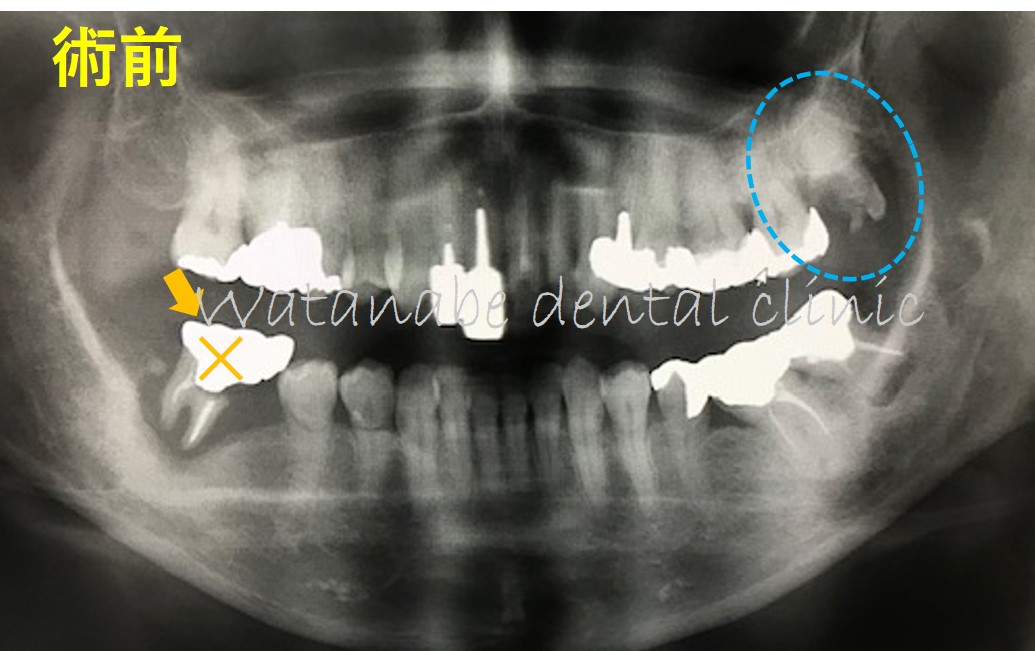

オレンジの×印の歯は根の先まで骨吸収があり抜歯するしか方法はありません。そこで、青〇の親知らずが放置され余っています。

そこで、オレンジ×の歯を抜歯して、青〇の親知らずを同部位へと移植する計画としました。